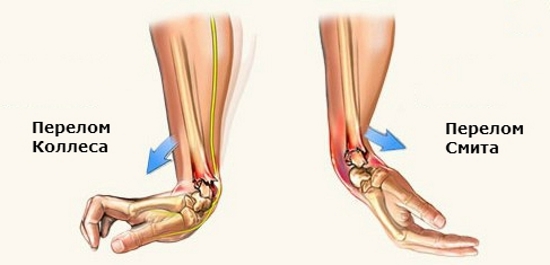

- Сгибательный (или перелом Смита). Данный вид перелома впервые был описан врачом Робертом Смитом, по имени которого и был назван, в 1847 году. Такое повреждение случается, если человек упал на руку, а кисть в это время была согнута в сторону тыльной стороны предплечья. При этом дистальный отдел лучевой кости смещается к наружной стороне предплечья.

- Разгибательный (перелом Колеса). Назван по имени ирландского врача, впервые описавшего такой перелом в 1814 году. Представляет собой зеркальное отображение перелома Смита, когда падение пришлось на ладонь, согнутую к внешней поверхности предплечья. При этом дистальный отдел смещается в тыльную сторону предплечья.